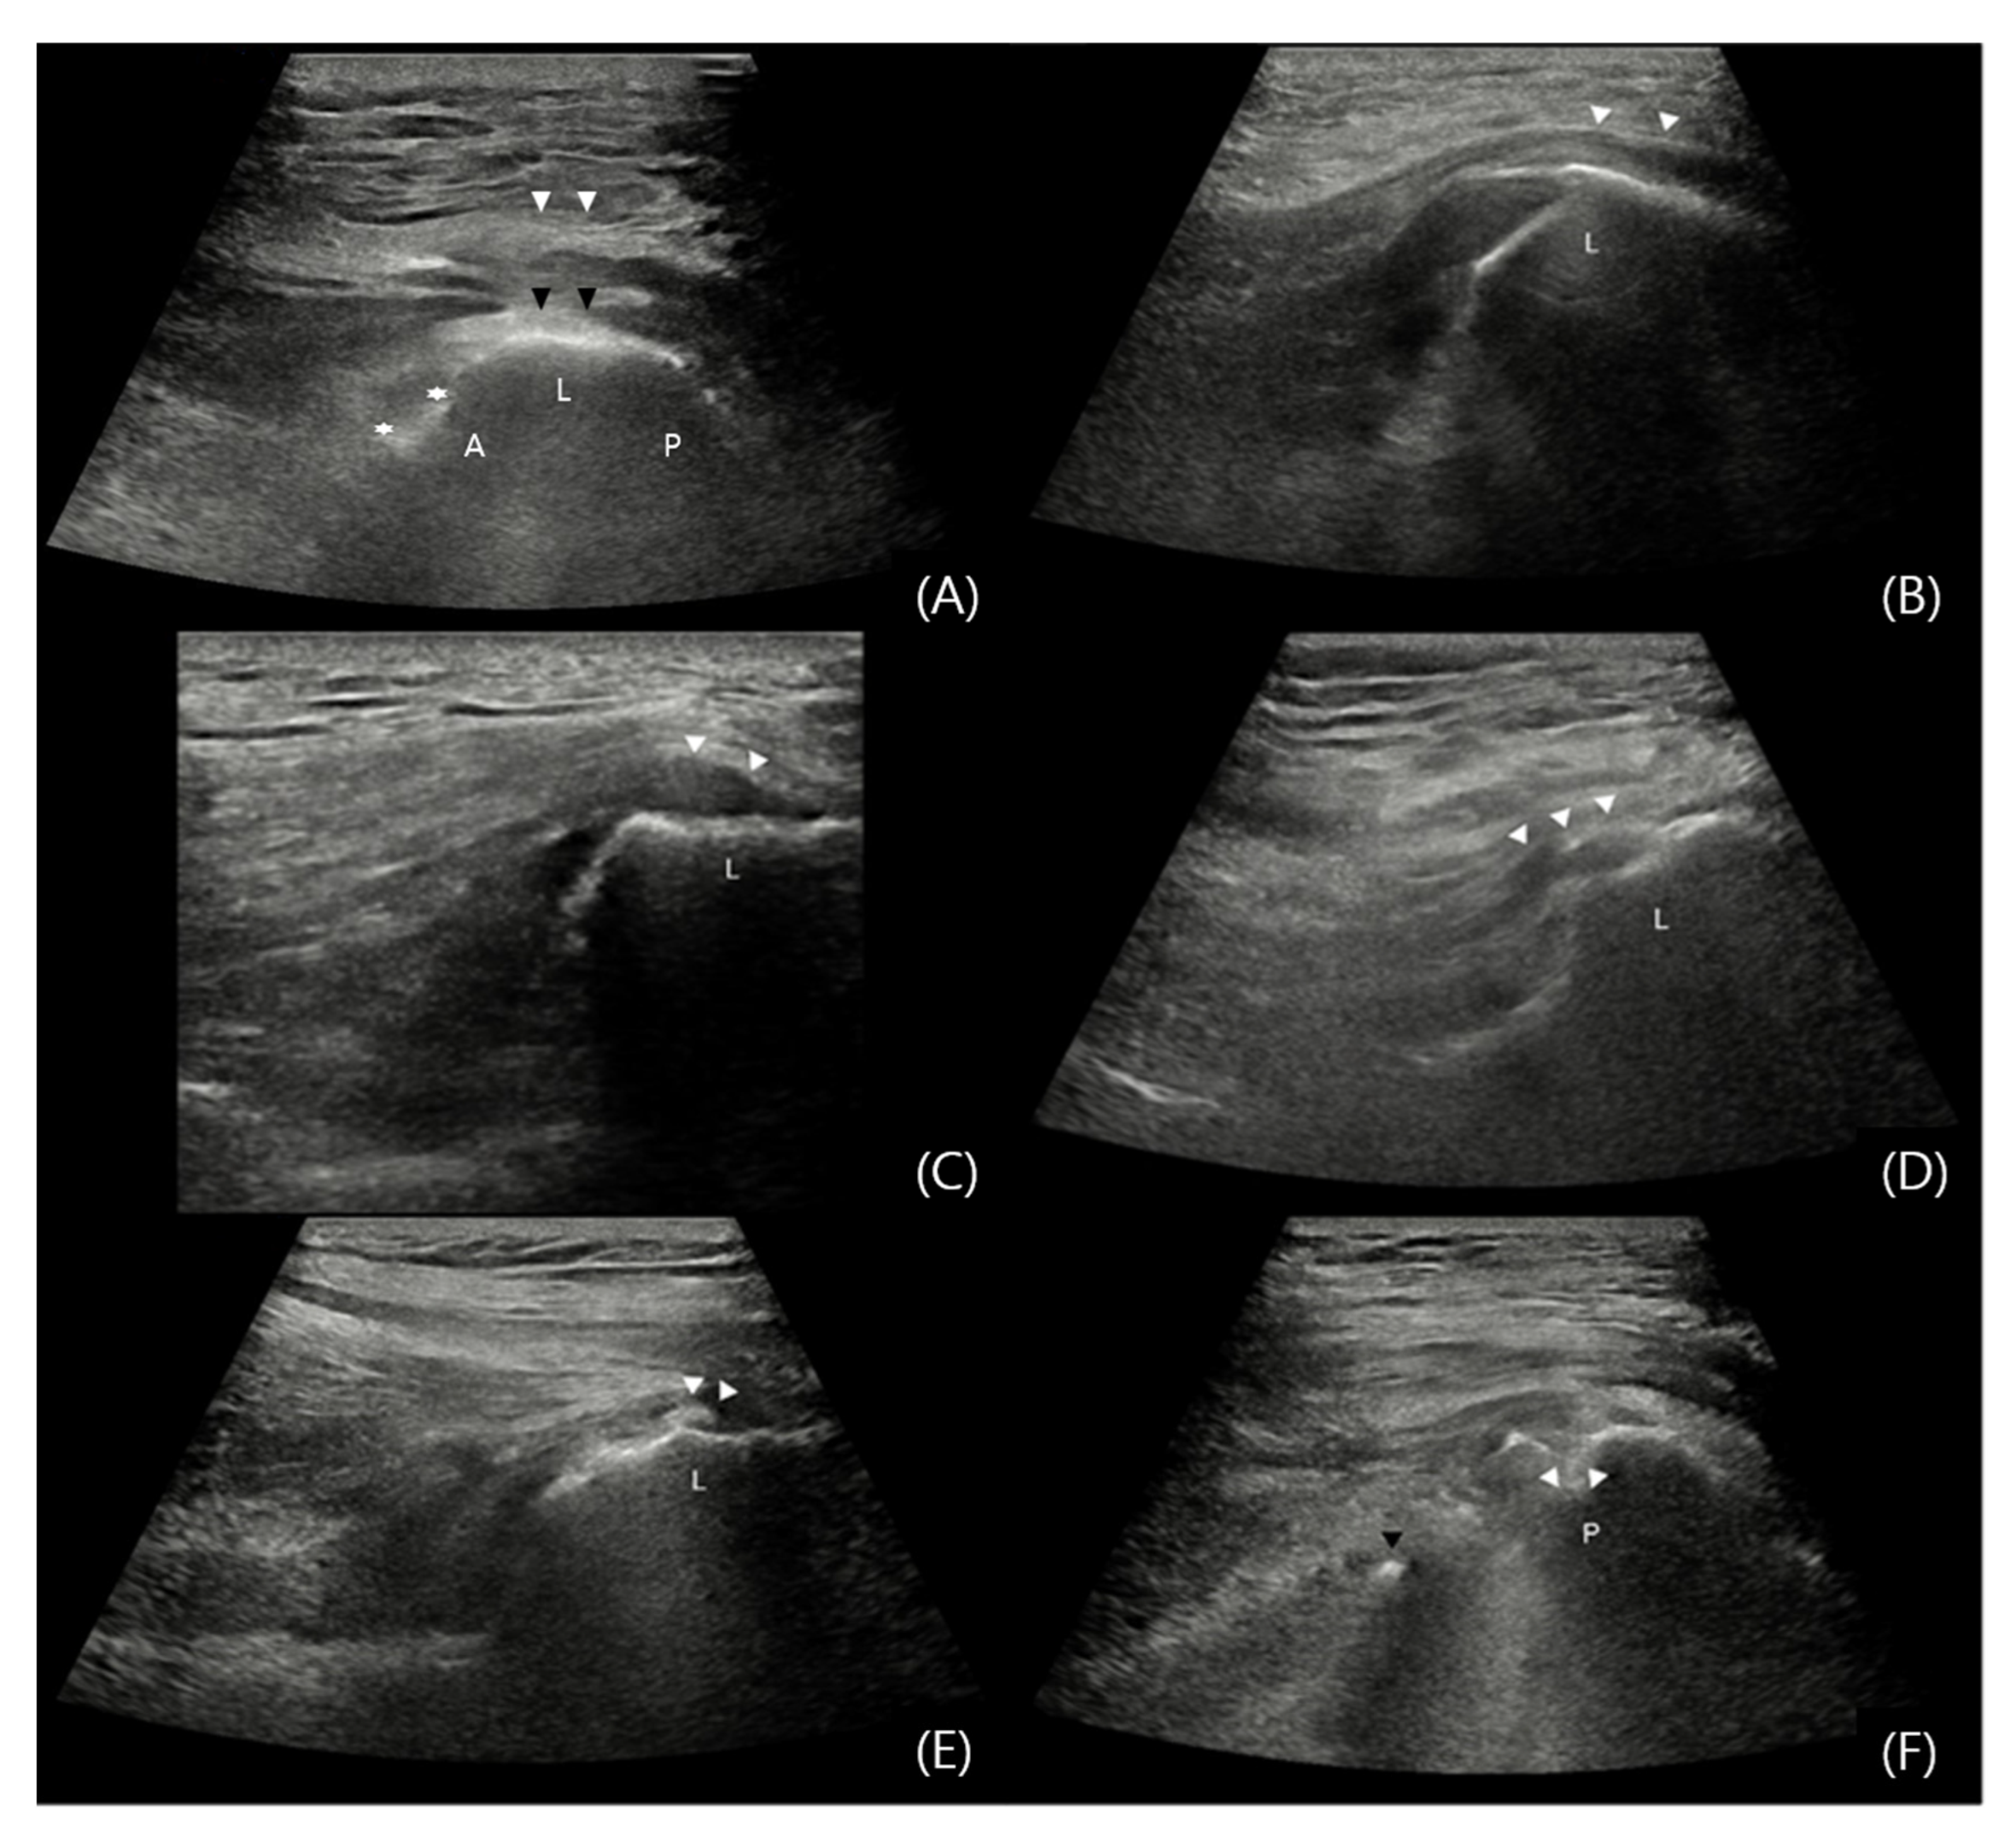

- Connell, D.A.; Bass, C.; Sykes, C.J.; Young, D.; Edwards, E. Sonographic evaluation of gluteus medius and minimus tendinopathy. Eur. Radiol. 2003, 13, 1339–1347. [Google Scholar] [CrossRef] [PubMed]

- Hilligsøe, M.; Rathleff, M.S.; Olesen, J.L. Ultrasound definitions and findings in greater trochanteric pain syndrome: A systematic review. Ultrasound Med. Biol. 2020, 46, 1584–1598. [Google Scholar] [CrossRef]

- Atilano, L.; Martin, N.; Iglesias, G.; Martin, J.I.; Mendiola, J.; Aiyegbusi, A.; Bully, P.; Rodriguez-Palomo, M.; Andia, I. Sonographic pathoanatomy of greater trochanteric pain syndrome. J. Ultrasound 2023, 27, 501–510. [Google Scholar] [CrossRef] [PubMed]

- Ruta, S.; Quiroz, C.; Marin, J.; Catay, E.; Rosa, J.; García-Monaco, R.; Soriano, E.R. Ultrasound evaluation of the greater trochanter pain syndrome: Bursitis or tendinopathy? JCR J. Clin. Rheumatol. 2015, 21, 99–101. [Google Scholar] [CrossRef]